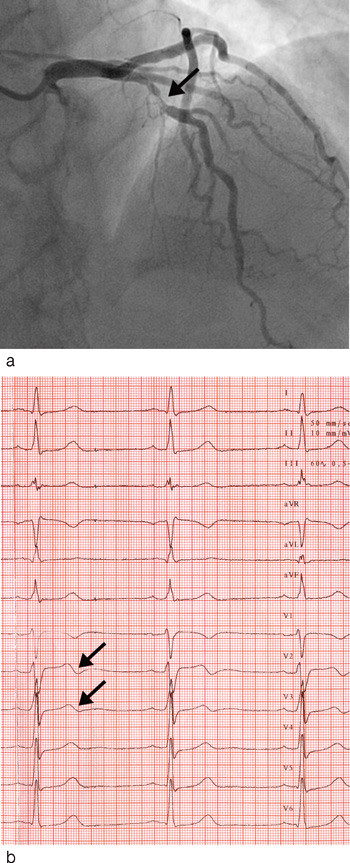

Negativ eller bifasisk T-bølge i V₂ – V₃ ble funnet oftere hos pasienter med iskemirelatert stenose i proksimalt i LAD enn hos de øvrige pasientene med akutt koronarsyndrom (76 % mot 11 %, p < 0,01) (tab 2, fig 1). Blant pasientene med negativ eller bifasisk T-bølge i V₂ – V₃ var det 61 % som hadde iskemirelatert stenose proksimalt i LAD. TIMI-risikoskår, maksimal troponin T, tid etter hospitalisering eller tid etter siste smerteanfall var ikke signifikant forskjellig mellom pasienter med og uten stenose proksimalt i LAD (tab 2). Heller ikke mellom pasienter med negativ eller bifasisk T-bølge i avledning V₂ – V₃ og de øvrige pasientene var det signifikant forskjell i disse variablene.

Bifasisk T-bølge ble funnet hos i alt 13 pasienter, og 11 (85 %) av disse hadde iskemirelatert proksimal stenose i LAD. Negativ T-bølge i V₂ – V₃ ble funnet hos 18 pasienter der åtte (44 %) hadde iskemirelatert stenose i proksimale LAD.

Wellens og medarbeidere beskrev to former for EKG-forandringer ved ustabil angina: isoelektrisk eller minimalt hevet (< 1,0 mm) ST-segment som går over i dyp negativ T-bølge, og bifasisk T-bølge med lett elevasjon i siste del av ST-avsnittet før brå overgang til negativ T-bølge (5, 7). Vi fant at de to mønstrene i EKG var om lag like vanlige ved stenose proksimalt i LAD. Selv om bifasisk T-bølge alene er mer spesifikt for proksimal LAD-stenose enn negativ T-bølge, er sensitiviteten liten siden funnet var til stede hos bare 44 % av våre pasienter. Pasientene med Wellens syndrom er vanligvis uten symptomer når EKG blir registrert, og forandringene i T-bølgen kan være eneste indikator på at et hjerteinfarkt er under utvikling av (7, 11). Under anfall med hvileangina kan de negative T-bølgene bli normalisert eller gå over i forbigående ST-segmentelevasjon (7, 11). I Wellens beskrivelse hadde 60 % av pasientene de karakteristiske EKG-forandringene ved innleggelse i sykehus, mens de øvrige utviklet negative eller bifasiske T-bølger 1 – 2 døgn etter innleggelsen (7). Vi fant ingen sammenheng mellom lengden av sykehistorien og påviste EKG-forandringer.